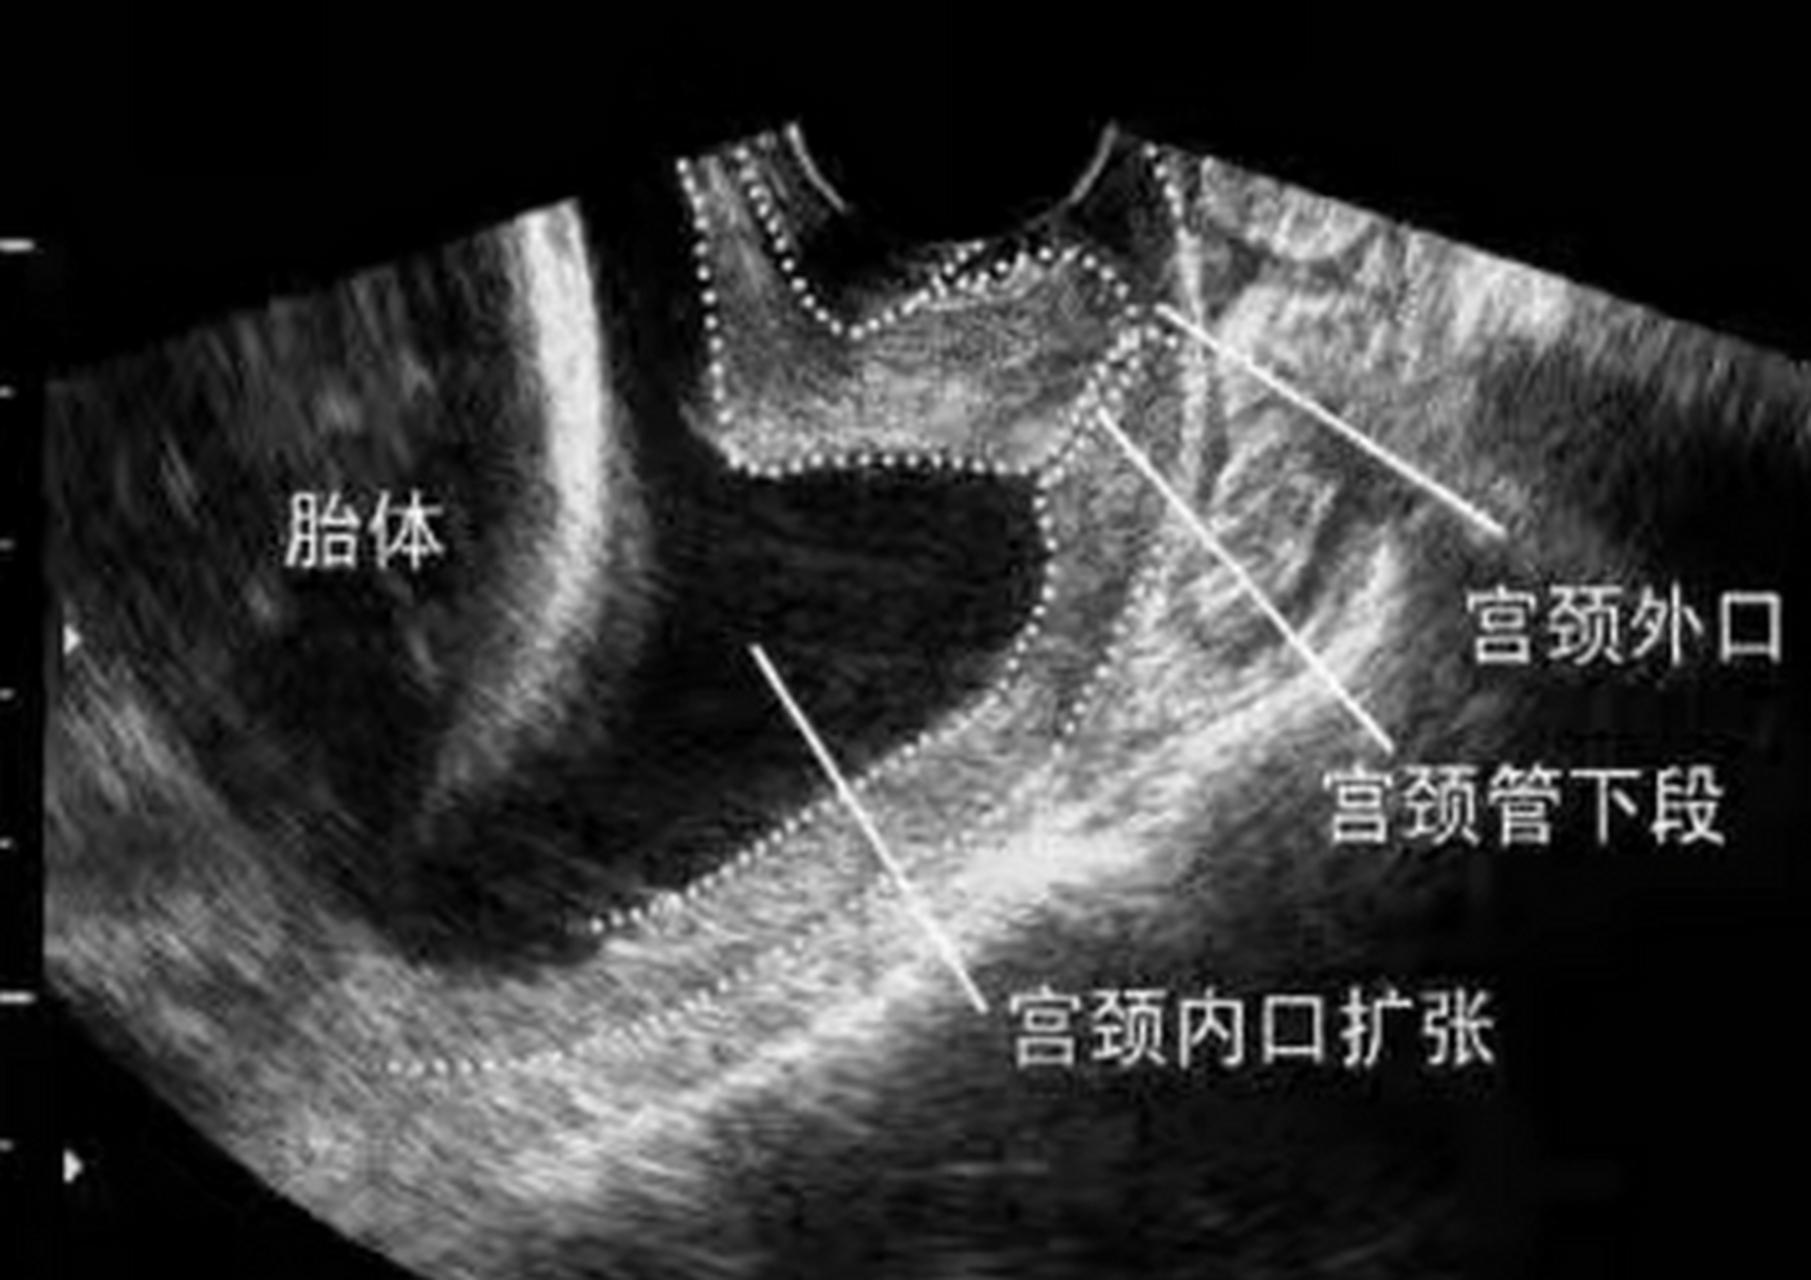

这项技术,让宫颈机能不全的孕妈妈们逆风"翻盘"_子宫_扩张_阴道

这种方法可以给宝宝一个安全的"家"|妊娠|早产|流产|会阴|子宫内膜